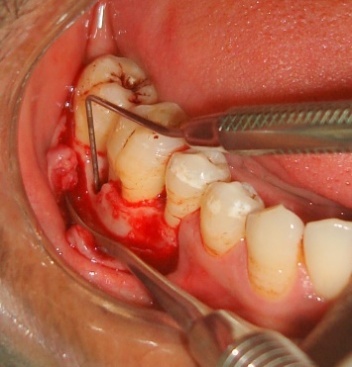

The treatment procedure was explained to the patient and a written consent was obtained. Initial periodontal therapy included patient education, oral hygiene instructions, thorough scaling and limited occlusal adjustments. The study protocol was approved by institutional review board and was in compliance with the Helsinki Declaration. Following all the surgical protocols, a mucoperiosteal flap was raised distal to the right mandibular second premolar to the right mandibular second molar teeth two millimeter beyond the defect (Figure 1). Complete debridement of the defect was carried out followed by extraction of the impacted maxillary right third molar.

Figure 1. Intrabony defect distal to the right mandibular first molar.